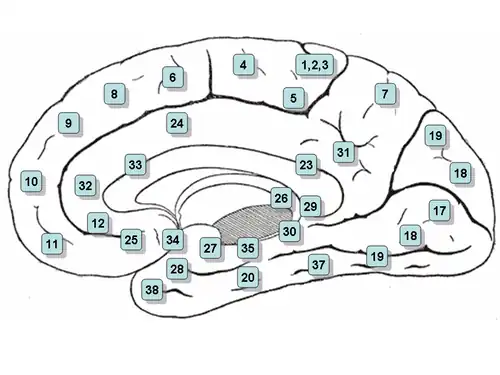

Na základě mozkové cytoarchitektoniky byla rozdělena na Brodmannovy oblasti 23, 24, 26, 29, 30, 31, 32 a 33 . Oblasti 26, 29 a 30 jsou obvykle označovány jako retrospleniální oblasti.

Střední povrch mozkové hemisféry. Střední pohled. Hluboká pitva.